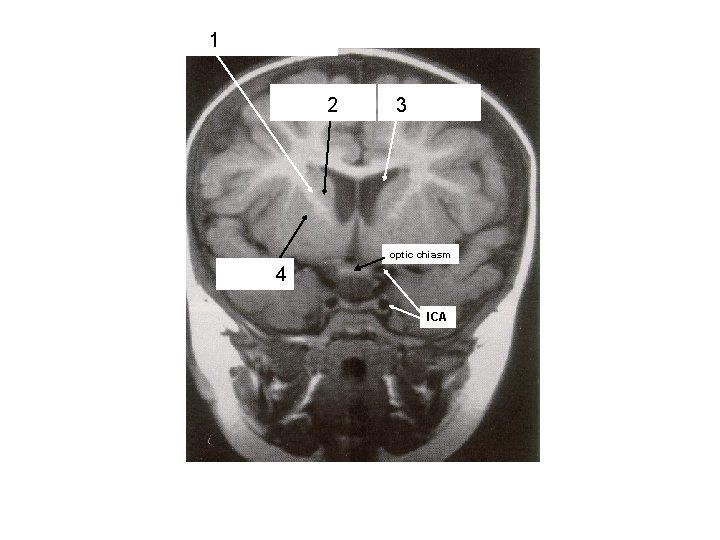

1 2

1 2 3

1 Thalamus 2 3 4

1 Thalamus 2 3 Lentiform Nucleus

1 2 Putamen 3 (lentiform nucleus)

ant. limb, Int. capsule (frontal eye field fibers) 1 head of caudate nucleus 2 frontal horn, lateral ventricle 3 optic chiasm 4 putamen ICA

Post. limb, int. capsule: corticospinal + corticopontine 2 + thalamocortical fibers Body 3 of lateral ventricle thalamus 4 descending cortical 1 fibers in crus cerebri of midbrain 5 Ventricle III Lentiform nucleus 6 putamen is visible) (only